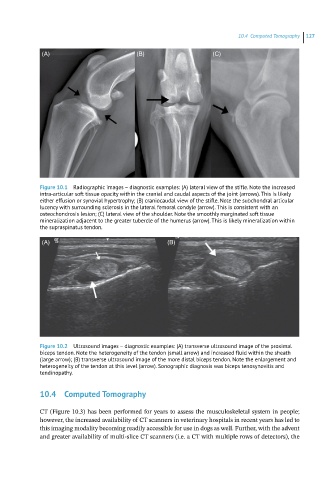

Figure 10.1 Radiographic images – diagnostic examples: (A) lateral view of the stifle. Note the increased

intra‐articular soft tissue opacity within the cranial and caudal aspects of the joint (arrows). This is likely

either effusion or synovial hypertrophy; (B) craniocaudal view of the stifle. Note the subchondral articular

lucency with surrounding sclerosis in the lateral femoral condyle (arrow). This is consistent with an

osteochondrosis lesion; (C) lateral view of the shoulder. Note the smoothly marginated soft tissue

mineralization adjacent to the greater tubercle of the humerus (arrow). This is likely mineralization within

the supraspinatus tendon.